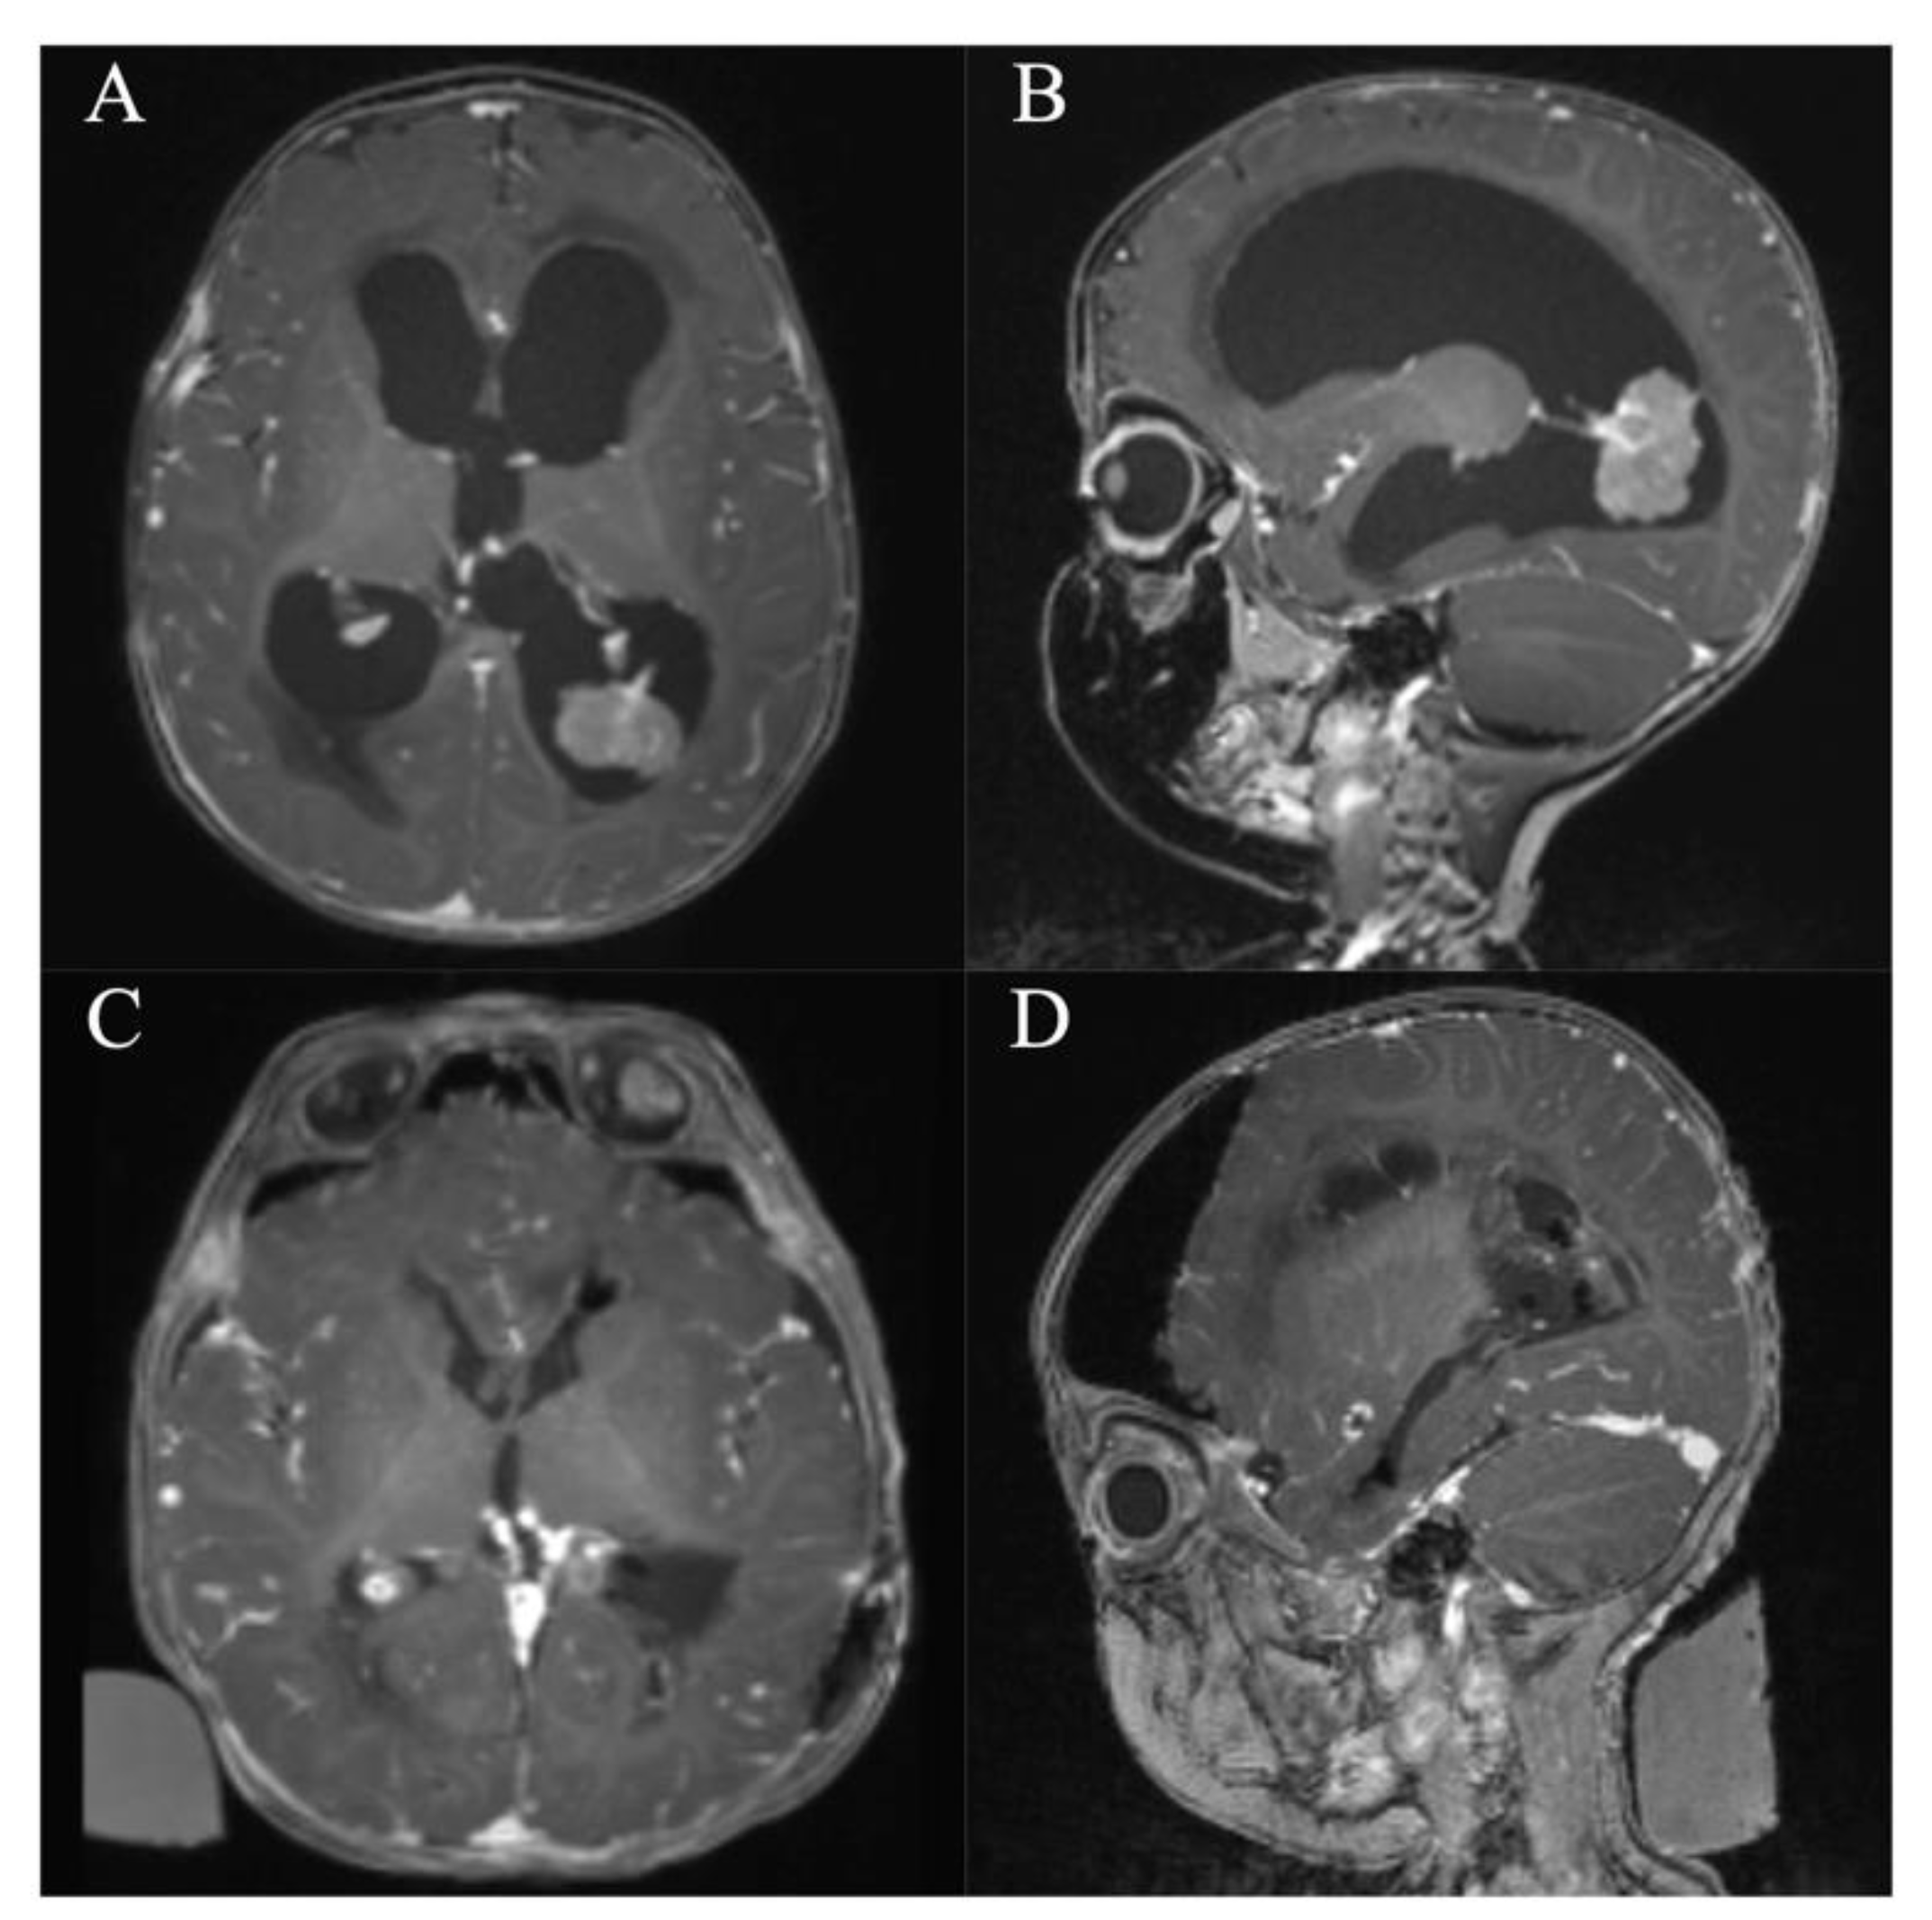

In all patients, a GTR/NTR could be achieved (Table 3). The pre- and postoperative scans of cases no. 3, 6, and 7, which were all treated through an EA approach and case no. 8, which was treated through a PE approach, are shown in Figure 3, Figure 4, Figure 5 and Figure 6. In one patient (case no. 5), due to her advanced age, we referred from resecting the vascularized capsule of the colloid cyst, achieving NTR. The mean surgery time was 163.6 ± 54.2 min (range 82–240 min) and the average blood loss was 142.5 ± 90.4 mL (range 50–300 mL). The PE approach was associated with lower mean blood loss than the EA approach (87.5 ± 47.8 mL vs. 197.5 ± 93.2 mL, p = 0.114). In four patients (50%), a total of six postoperative complications occurred, of which all were transient. Two patients (25%) showed transient cognitive impairments after resection of a colloid cyst, most likely directly associated with the endoscopic approach. The remaining four transient complications were unrelated to the use of endoscopy or NUA (Table 3). The two patients with neuropsychological evaluation showed postoperatively scores of 18/30 and 25/30 points, respectively, with a documented improvement in both patients at follow-up (18/30 to 24/30 points within 35 days and 25/30 to 30/30 points within 114 days). With regards to the remaining adult patients, no evaluation was carried out, because there was no evidence of neurocognitive deficits subjectively. In the two children with intraventricular lesions, no postoperative neurocognitive assessment was performed (due to autism disorder in the context of tuberous sclerosis in one case and due to the very young age of 5 months in the other case) (Table 3). At follow-up (15.9 ± 6.3 months; range 6.8 to 23.2 months), all patients showed improved or unchanged mRS when compared to the mRS at discharge. Complete regression or improvement of the preoperative complaints was seen in all patients, while MRI at follow-up showed no recurrence in any of the cases (Table 3).

Figure 4. Case 6. Axial and sagittal MR images, T1-weighted sequences with contrast medium preoperatively (A,B) and immediately postoperatively (C,D) after resection of the intraventricular choroid plexus carcinoma via a left occipital endoscopic-assisted approach.